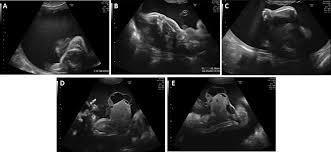

Paternal Uniparental Disomy For Chromosome 14 Prenatal Management Bmj Case Reports